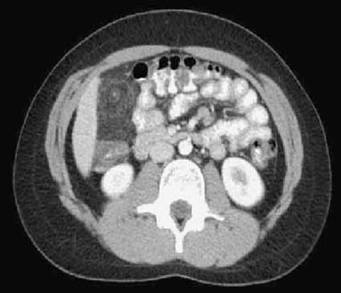

Figura 19-2. Tomografia computadorizada do abdome, no qual se nota, à direita, posteriormente à parede abdominal anterior, área de aumento da atenuação da gordura mesentérica, com realce central.